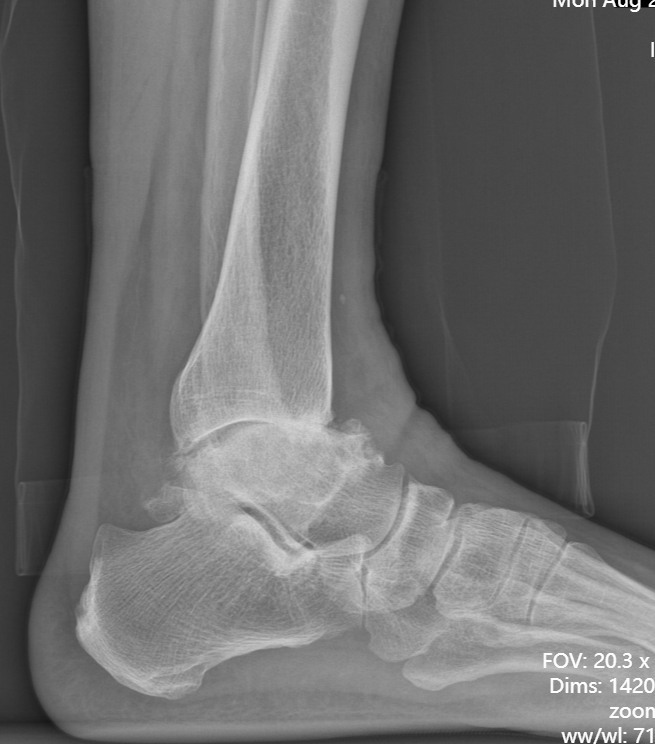

第一台手术的患者是位75岁的叔叔,被“脚脖子”痛缠了4年,疼得越来越厉害,病情已经到了严重阶段。

术前后足力线X线

武勇主任团队给他做了3D打印导板辅助下人工全踝关节置换术。

这种手术适合踝关节病严重的患者,通过替换病变的关节结构,能帮着缓解疼痛、恢复关节活动,让老人日常走路更自在些。